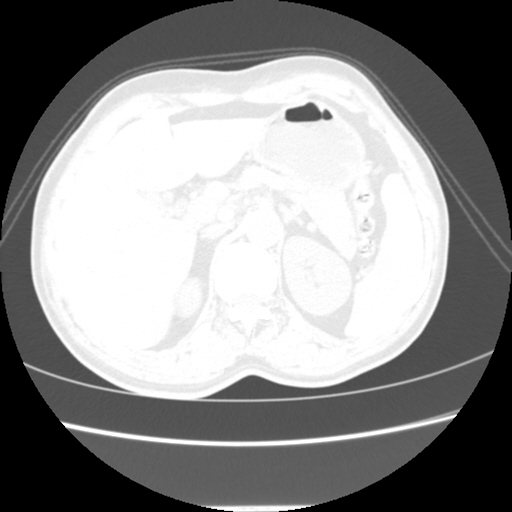

A 62 years old man with enlarged mole on chest since 2 months.

CT chest :-